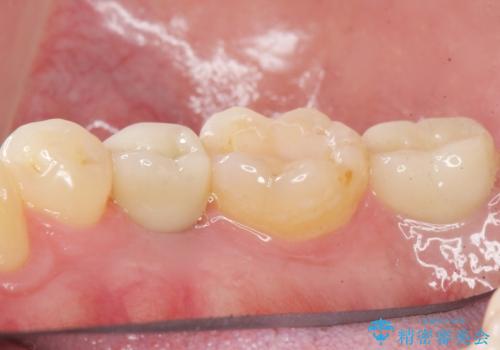

予算を抑えてしっかりとしたインプラント治療 30代男性

- 奥歯(右下5)のインプラントをご希望し来院された患者様です。

なるべく低予算でとのご希望により、アルファタイトインプラント(保証期間:3年)による治療を行いました。

自然な仕上がりと咬み心地に喜んで下さいました。

「低予算でしっかりした治療を受けることができた」とご満足頂けました。

インプラントの種類:アルファタイト

クラウンの種類:オールセラミッククラウン スタンダード